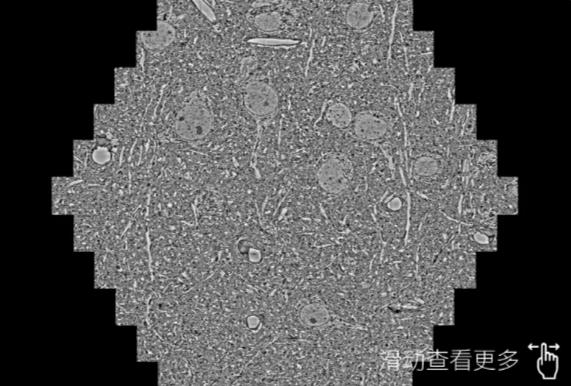

鼠脑切片。左图使用惠州蔡司惠州扫描电镜MultiSEM706对165μmx143pm面积区域成像,耗时仅需1.5秒。右图为鼠脑切片中30μm区域放大效果。样品由芝加哥大学B.Kasthuri提供。

使用蔡司高速惠州扫描电镜MultiSEM对1mm²人脑皮层组织进行高分辨成像,并对其中的各种细胞结构进行三维重构分析。左图展示了2x3mm²组织平面中锥体神经元的三维重构效果。右图显示了局部体积神经元三维重构。图像由哈佛大学chtman实验室提供,渲染图由D. Berger 制作。